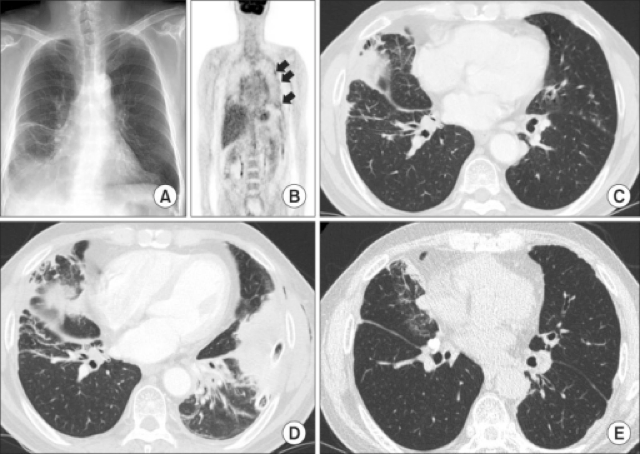

Mesothelioma is a rare and aggressive tumour with dismal prognosis arising in the pleura and associated with asbestos exposure. Intrathoracic Manifestations of IgG4-Related Disease | Lim

The systemic treatment of malignant pleural mesothelioma (mpm) in routine practice has remained unchanged since 2003, with almost a decade passing since any . Intrathoracic Manifestations of IgG4-Related Disease | Lim

Intrathoracic Manifestations of IgG4-Related Disease | Lim from pulmonarychronicles.com